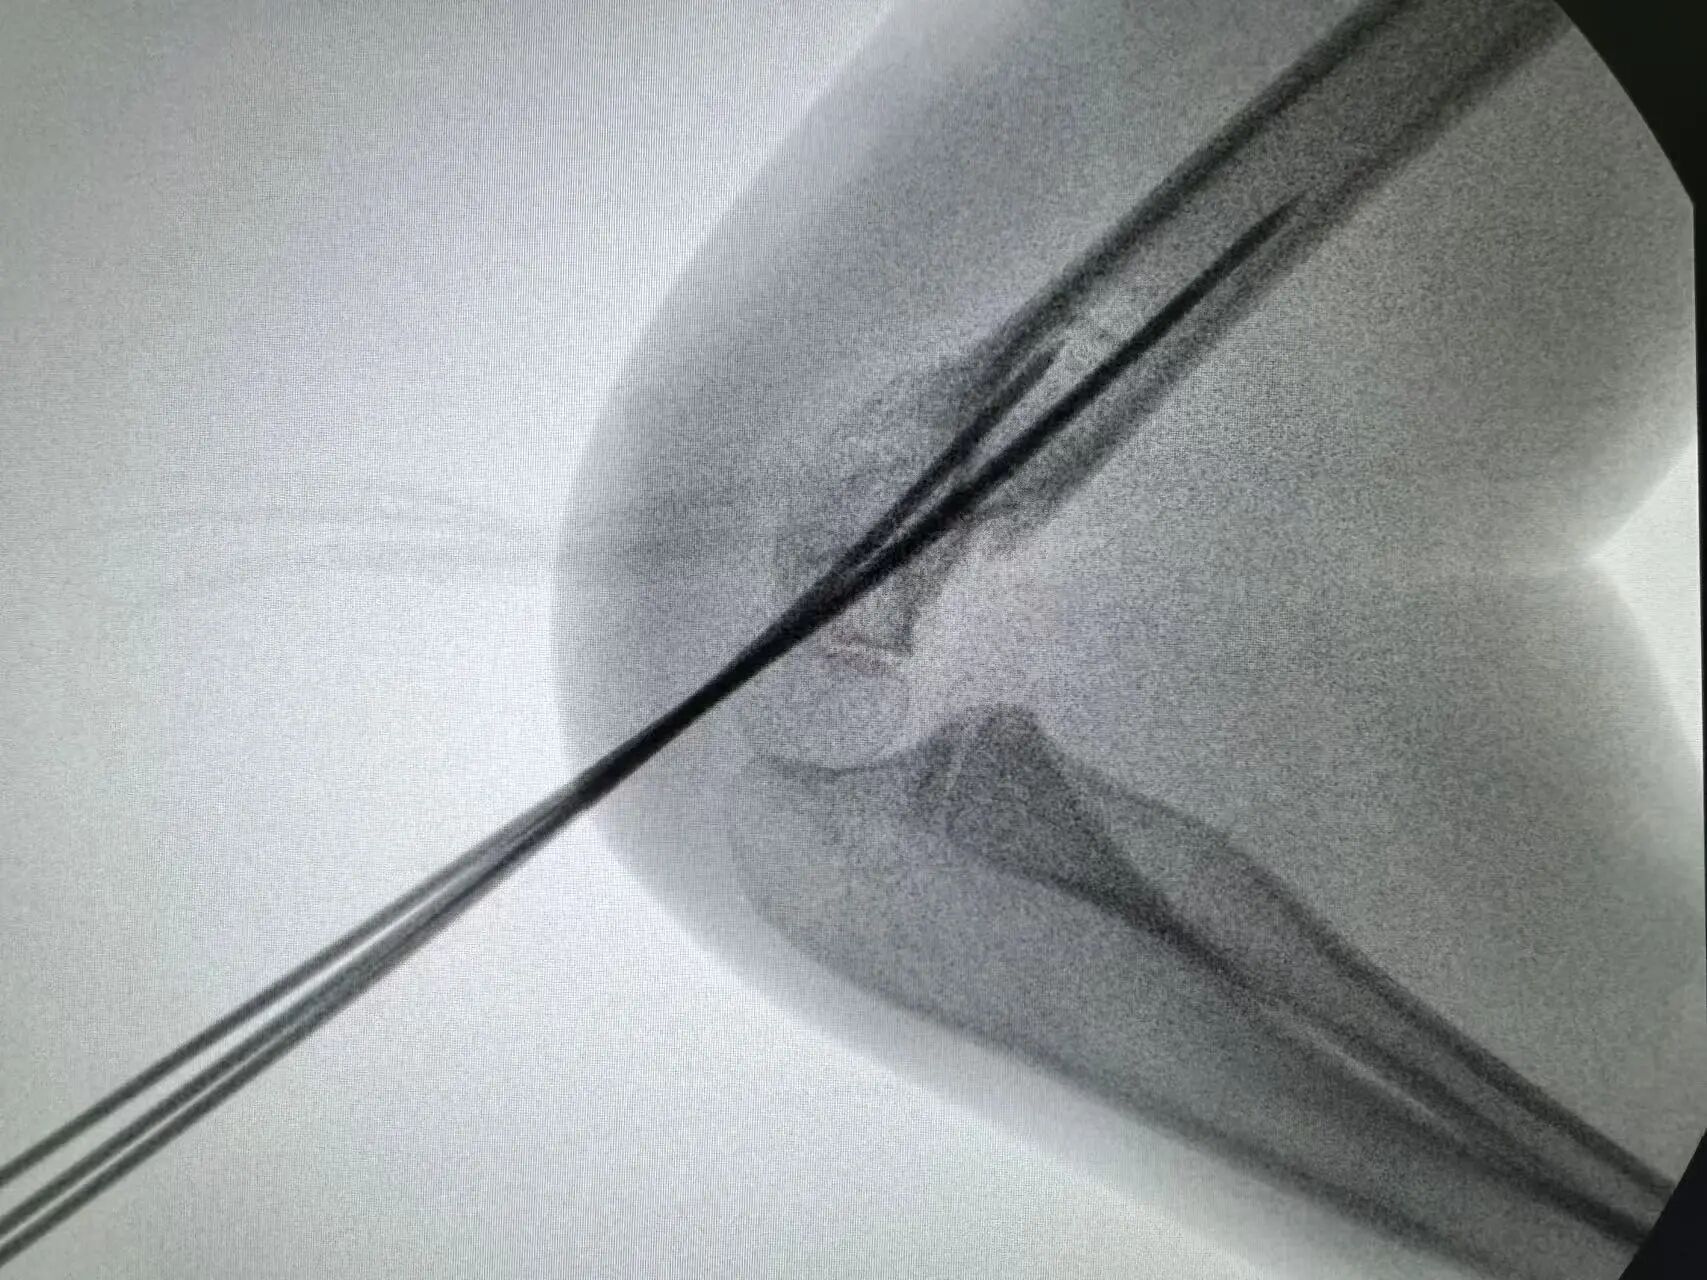

同样“抢时间”的还有小罗和小周的治疗:4岁小罗9月15日深夜入院,10小时后顺利手术;7岁小周同一晚受伤,也在10小时内完成肱骨髁上骨折闭合复位经皮固定术。6岁小郑更是创下“4小时极速手术”纪录——早晨7点40分受伤,8点多入院,11点多手术结束,当天下午就能躺上网课。

“我们的目标是‘24小时内完成急诊手术’,尽量让孩子少耽误一节课。”骨伤科手外·儿骨·烧伤整形组主任陈孝均教授介绍,为了实现这个目标,团队制定了专属流程:孩子入院后,急诊优先开具检查单,放射影像科快速出片;骨科医生同步评估病情,确定手术方案;麻醉科提前做好准备,只要术前检查合格,立刻安排手术——哪怕是深夜或周末,团队也随时待命。